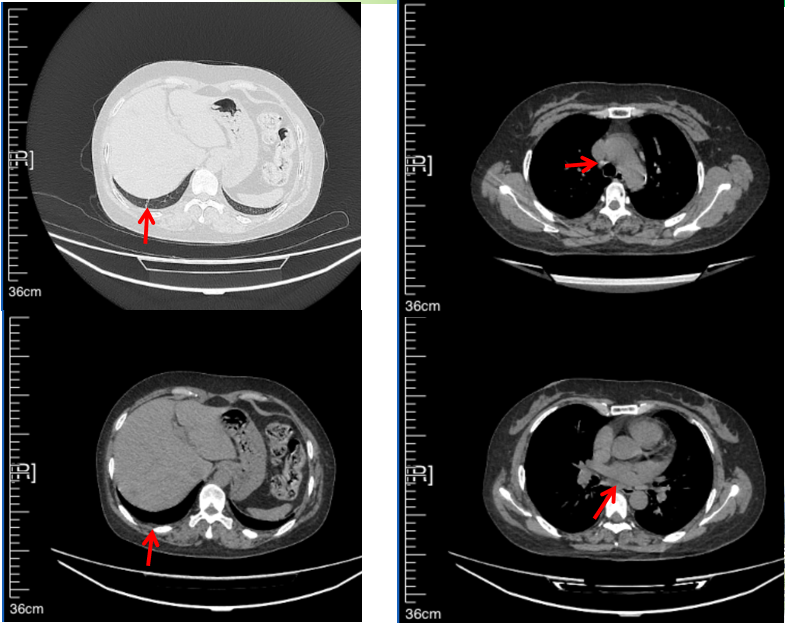

2016年1月复查CT提示支气管截断可见新发小结节,一线治疗采用培美曲塞+DDP方案化疗4周期(培美曲塞3.36,DDP 480mg)。化疗后复查胸部CT:右肺见不规则结节样影,最大层面大小约19mm*8mm,较前比较明显增大,疗效评估PD。2017.3-2017.4予单药多西他赛化疗3周期,疗效评估SD。2018年5月末复查CT提示结节较前增大,评效为PD,2018年6-10月予多西他赛+CBP化疗4周期,疗效评估SD。2022年5月患者出现活动后气短,复查胸部CT示右肺膨胀不良;右侧胸腔积液增多。胸腔积液包埋病理示符合肺腺癌细胞。行NGS基因检测:EML4:exon13-ALK:exon20融合。PD-L1(克隆号22C3)TPS<1%。

2018.07

2022.05

2022.08

2023.05

2024.12